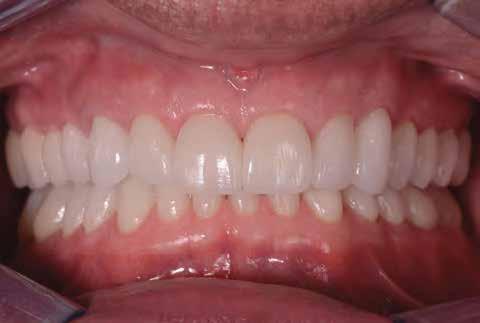

A fogak extrahálása és az alveoláris plasztika teljes narkózis mellett történt meg, így teremtve ideális helyzetet a protetikai ellátáshoz. A műtéti beavatkozás után a páciens az ideglenes fogsorral távozott. Egy héttel később jött kontrollra. Nemcsak látványra változott meg nagymértékben, hanem egyértelműen magabiztosabb és önbizalommal teli volt a fellépése (12. ábra)

Az elsődleges terápiás szakasz kulcsfontosságú volt a teljes rehabilitáció szempontjából. A páciensnek nem csak szép, esztétikus mosolyt kölcsönzött, hanem életminőségének javulását is hozta (13. ábra). A Digital Denture folyamatnak köszönhetően a kezelés ráfordításai is alacsonyak voltak. A fiatal nő messzemenően boldog, magabiztos és motivált a következő lépéshez.